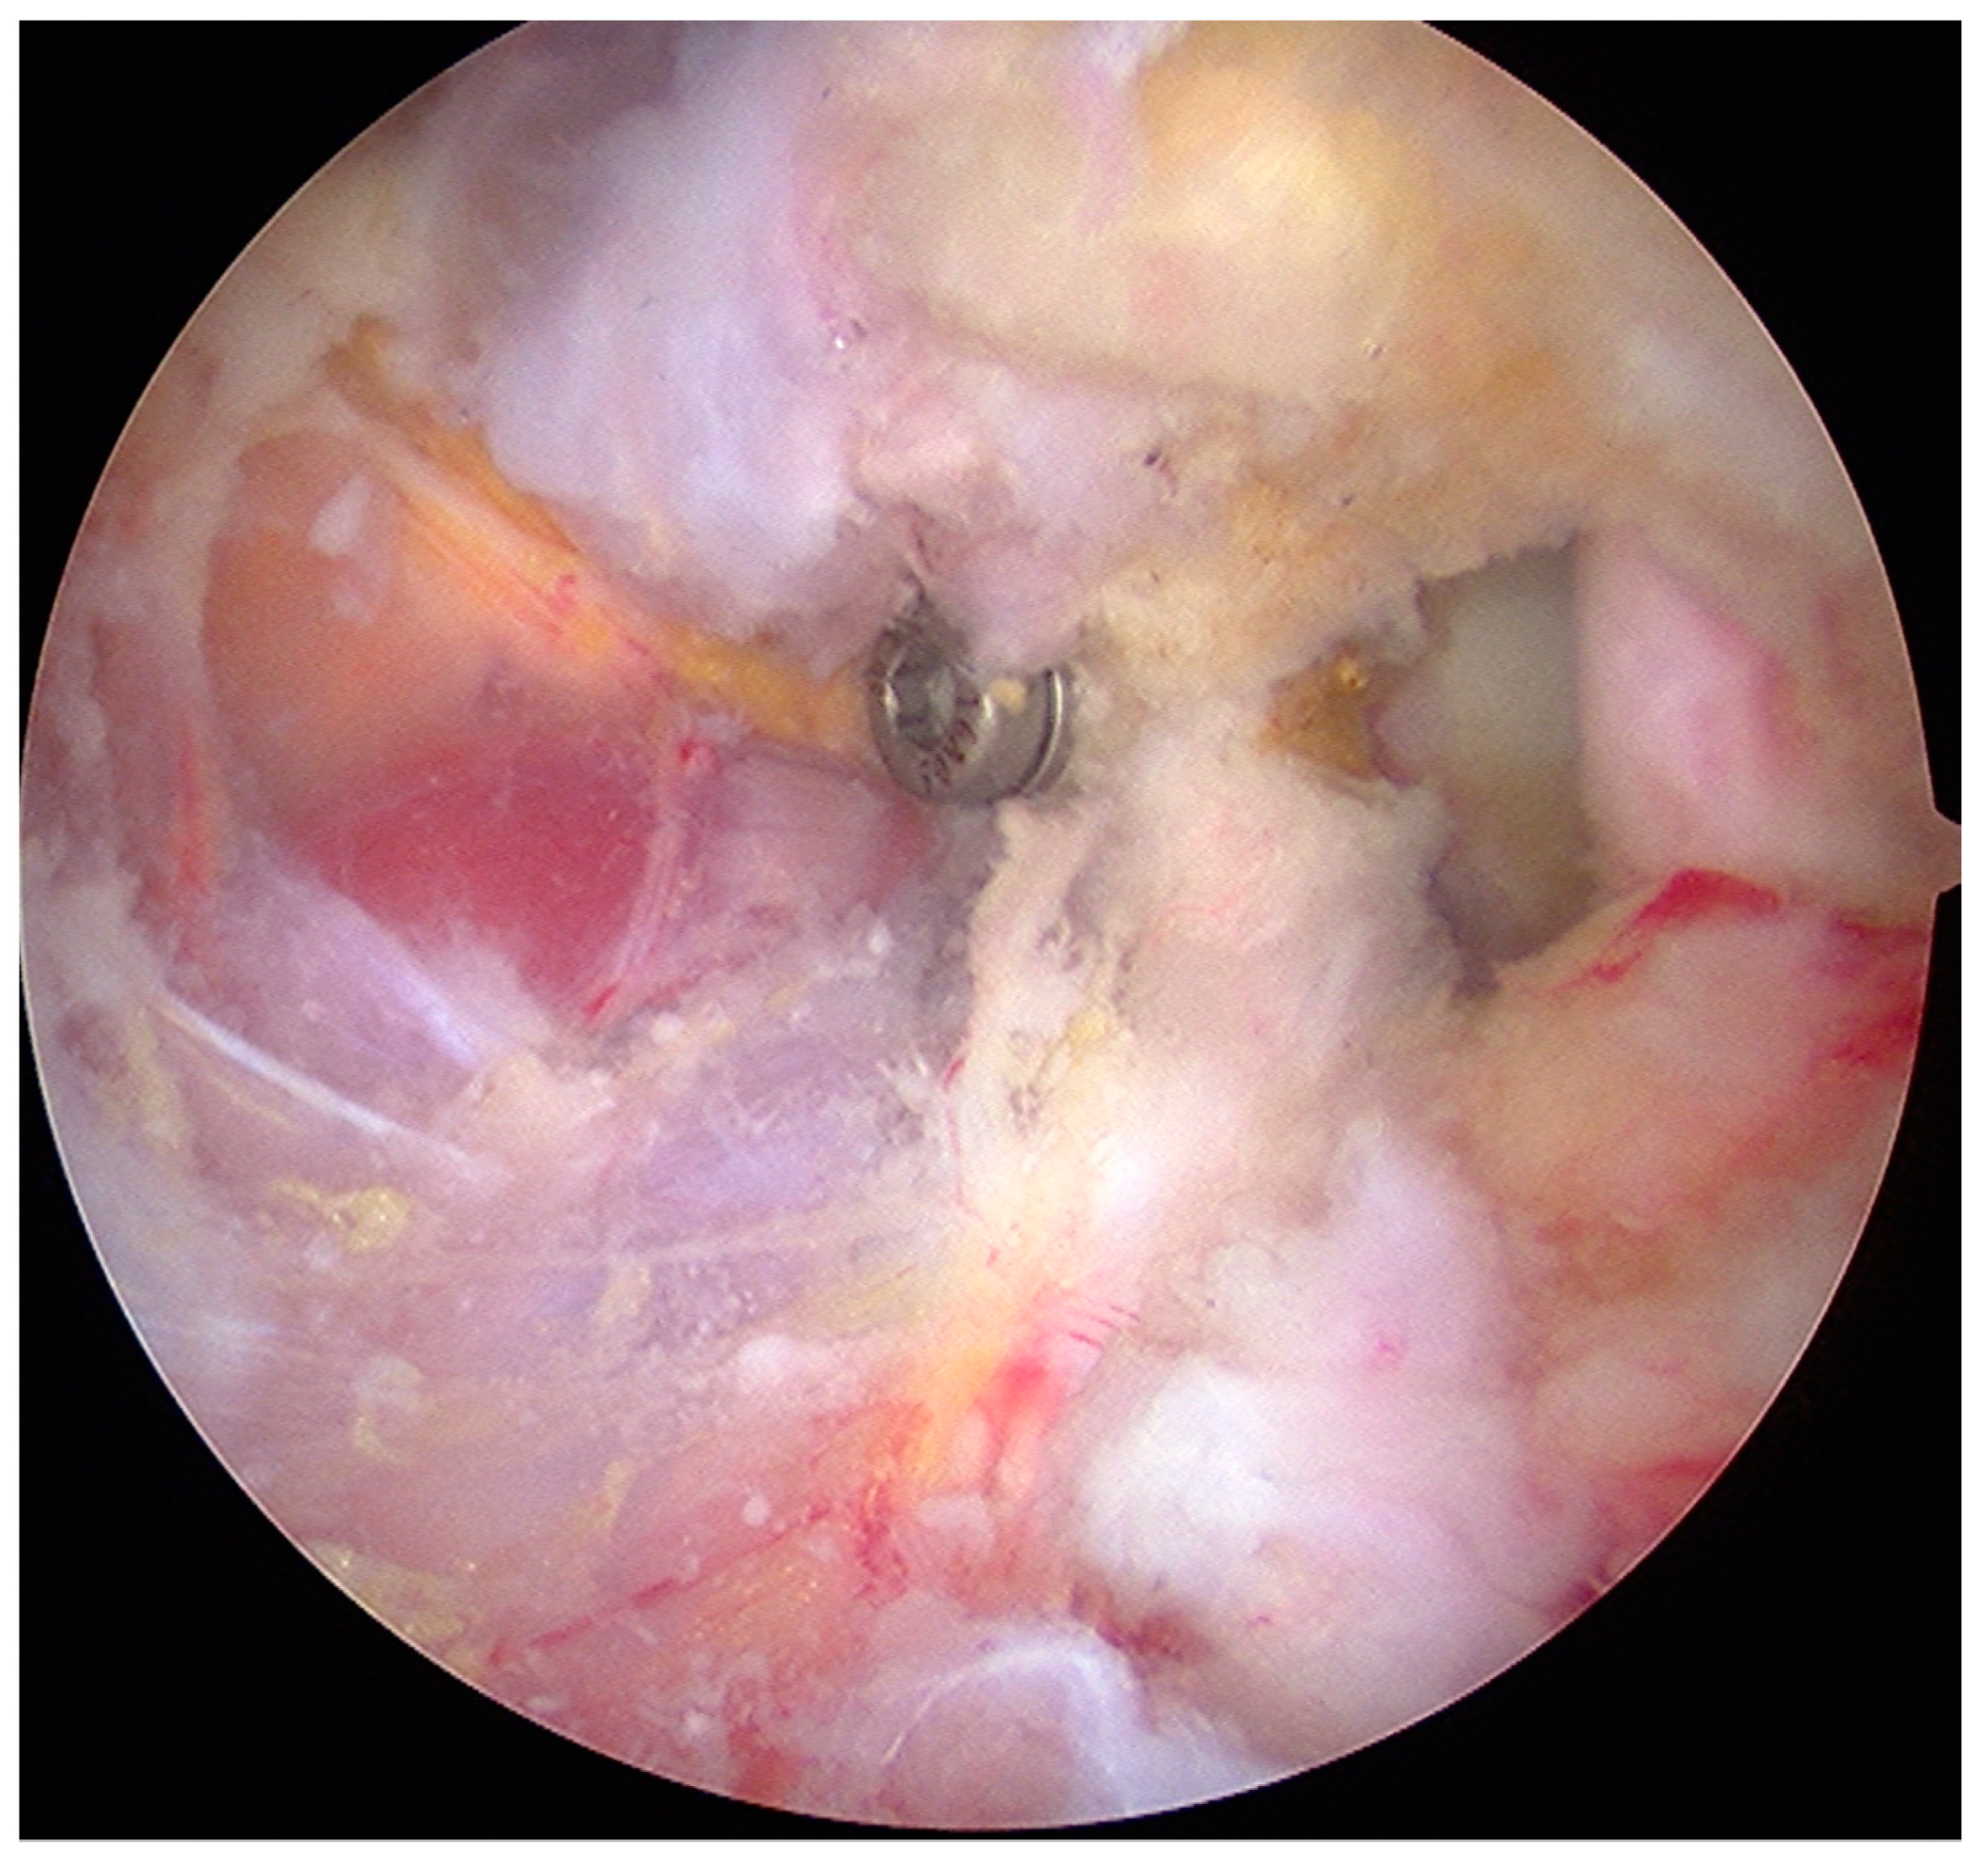

- The graft was fixed. Two holes were made through the coracoid and the glenoid using the double cannula. Graft trimming was performed with the burr (Figure 4).